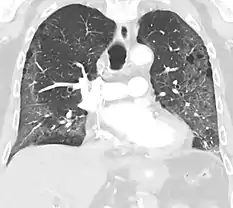

CT image showing mosaic attenuation pattern in patient with hypersensitivity pneumonitis. Note the alternating, patchy areas of increased and decreased attenuation, particularly in the left lung (screen right).

Mosaic

A mosaic pattern of GGO refers to multiple irregular areas of both increased attenuation and decreased attenuation on CT. It is often the result of occlusion of small pulmonary arteries or obstruction of small airways leading to air trapping.[6] Sarcoidosis is an additional cause of a mosaic GGOs due to the formation of granulomas in interstitial areas. This may coexist with granulomatosis with polyangiitis, leading to diffuse areas of increased attenuation with ground-glass appearance.[6]